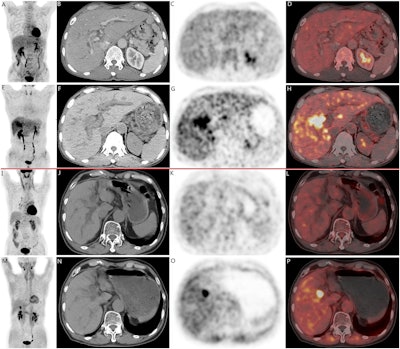

Two cases of pathologically confirmed intrahepatic cholangiocarcinomas in 68-year-old male patients. In both cases (A-H, case 1; I-P, case 2), CT scans (B, F, case 1; J, N, case 2) revealed intrahepatic bile duct dilation and suspected nodular lesions. While F-18 FDG PET/CT (A, C, D, case 1; I, K, L, case 2) failed to demonstrate abnormal tracer uptake (SUVmax 3.5, TBR 1.3 in Case 1; SUVmax 2.6, TBR 1.2 in Case 2), F-18 FAPI-04 PET/CT (E, G, H, case 1; M, O, P, case 2 ) showed positive uptake in the nodular lesions (SUVmax 9.7, TBR 3.5 in Case 1; SUVmax 9.6, TBR 3.3 in Case 2). Image available for republishing under Creative Commons license (CC BY 4.0 DEED, Attribution 4.0 International) and courtesy of BMC Cancer.